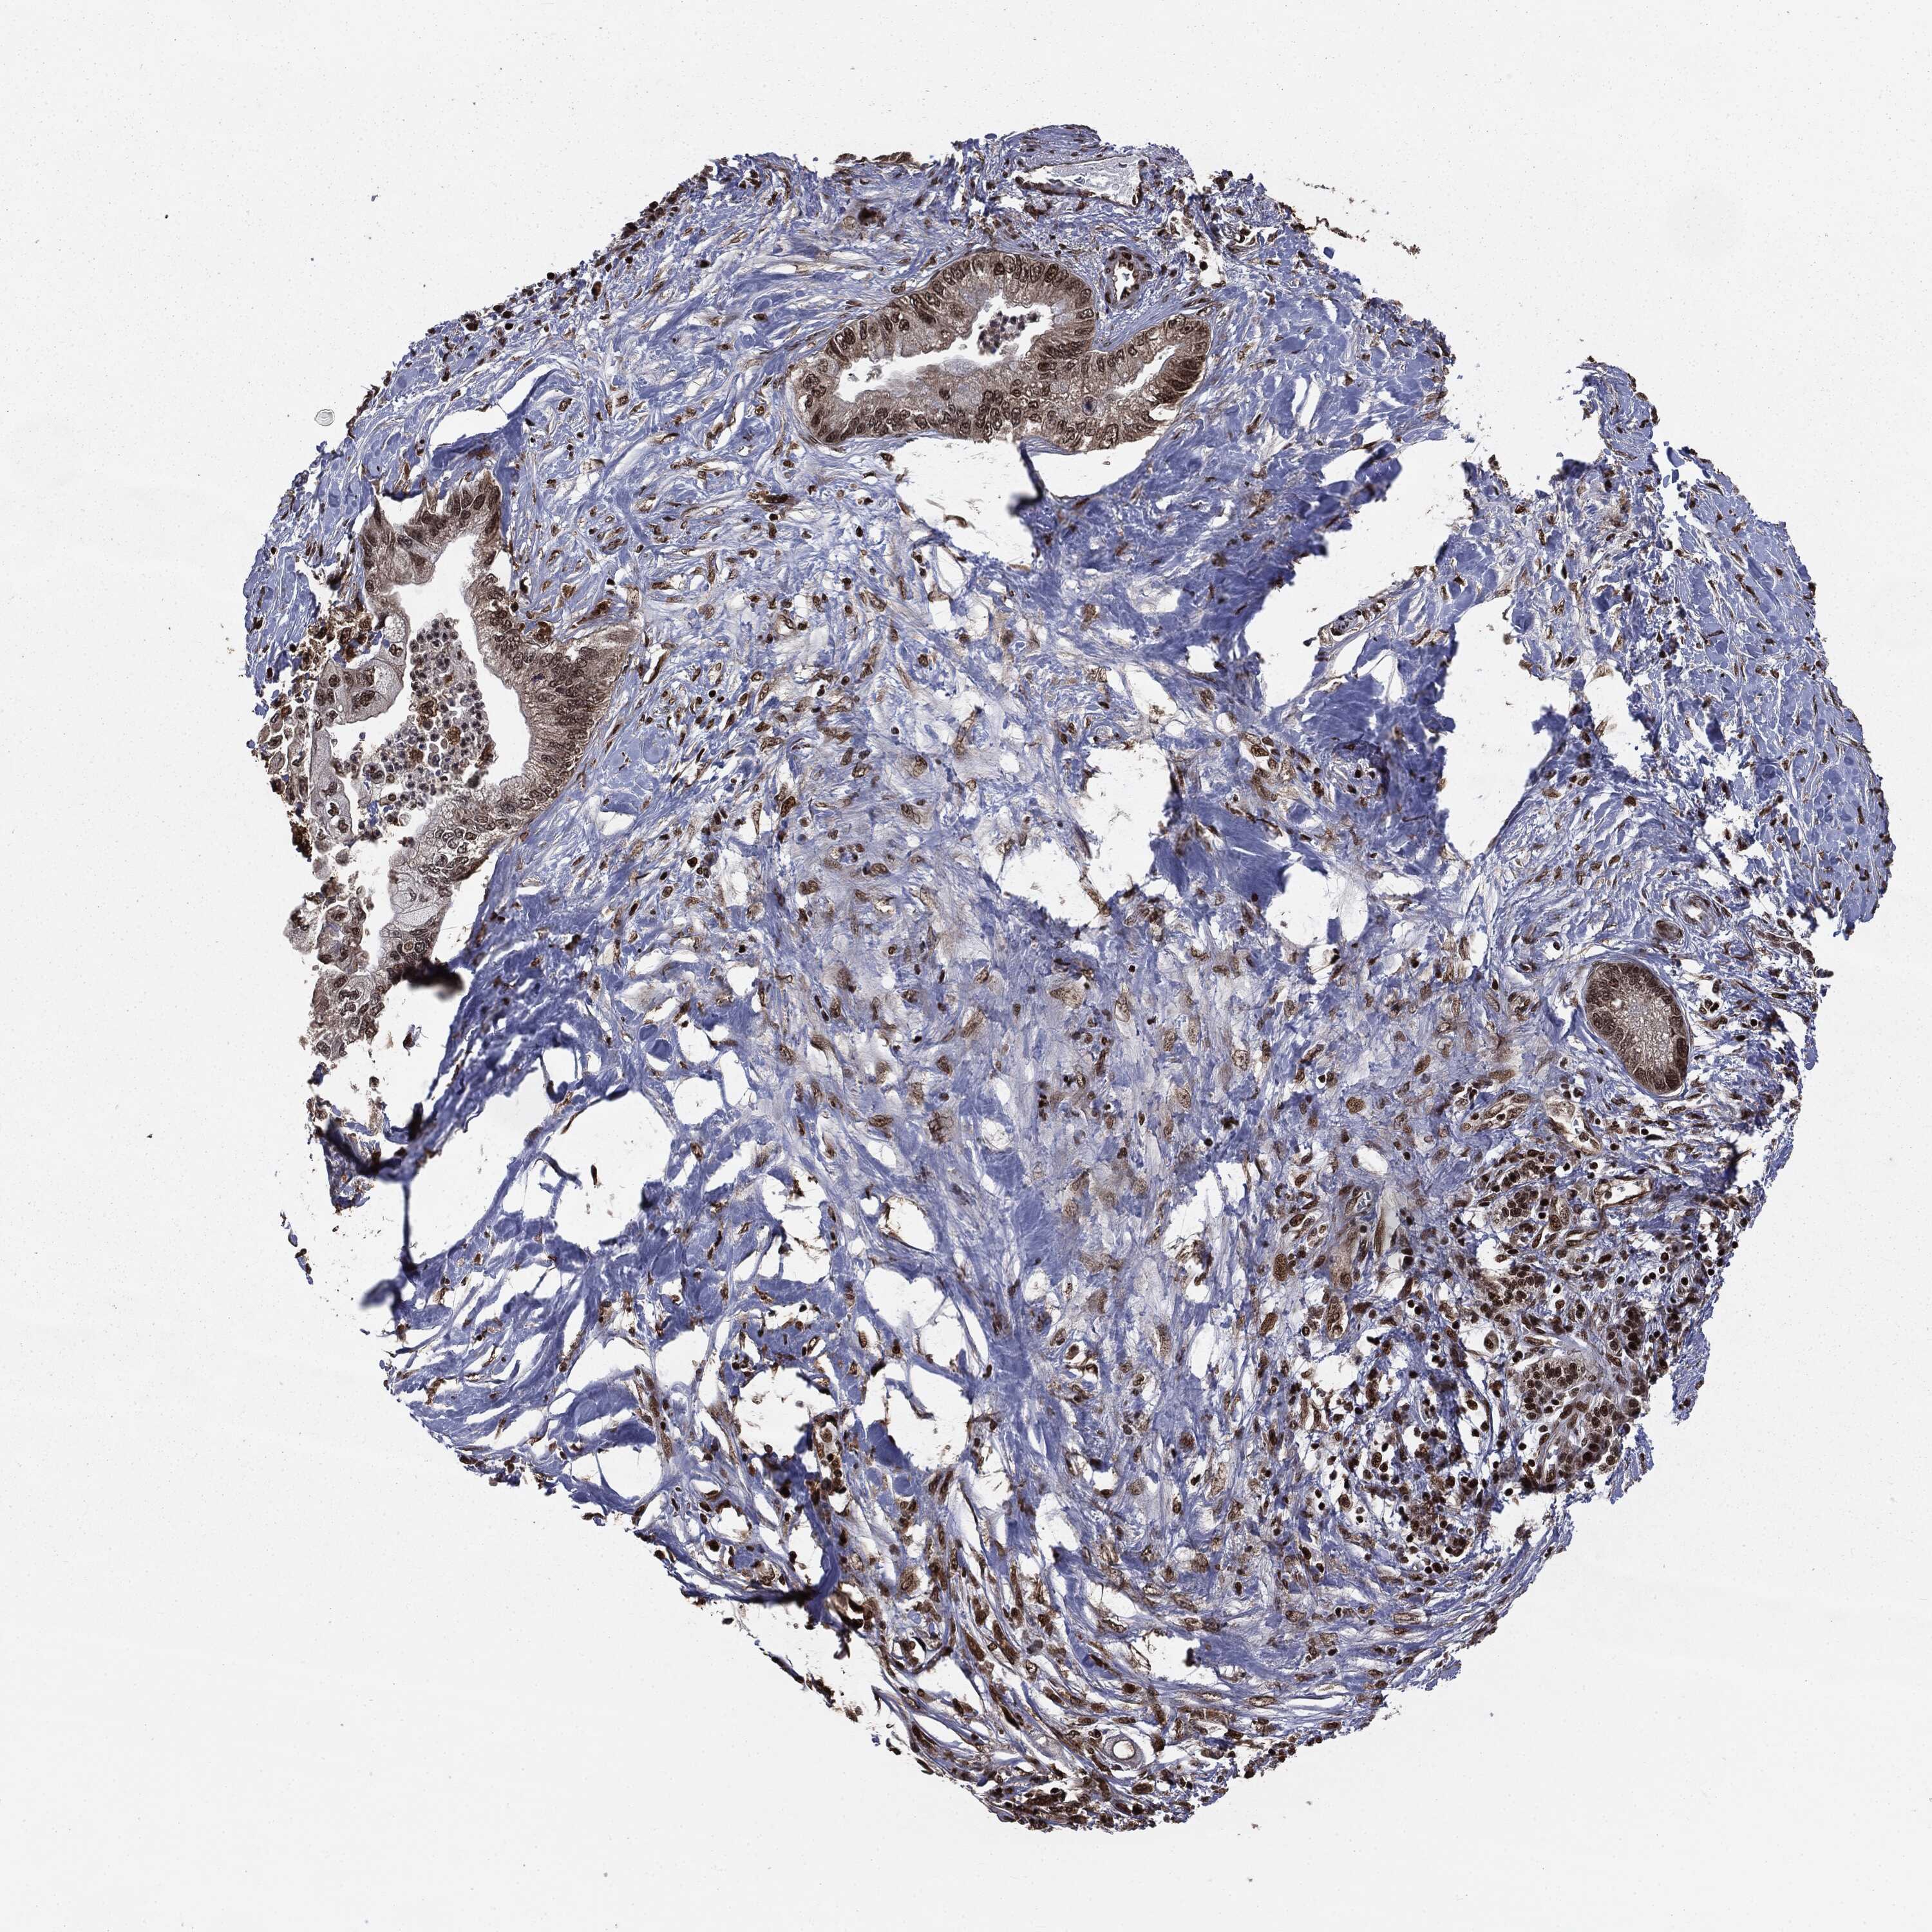

PANCREATIC CANCER - Protein expressioni

A mouse-over function shows sample information and annotation data. Click on an image to view it in a full screen mode. Samples can be filtered based on level of antibody staining by selecting one or several of the following categories: high, medium, low and not detected. The assay and annotation is described here.

Note that samples used for immunohistochemistry by the Human Protein Atlas do not correspond to samples in the TCGA dataset.

Antibody stainingi

Antibody staining in the annotated cell types in the current human tissue is reported as not detected, low, medium, or high, based on conventional immunohistochemistry profiling in selected tissues. This score is based on the combination of the staining intensity and fraction of stained cells.

Each image is clickable and will lead to virtual microscopy that enables deeper exploration of all samples and also displays staining intensity scores, fraction scores and subcellular localization as well as patient and tissue information for each sample.

Antibody HPA022914

Antibody HPA064732

Adenocarcinoma, NOS